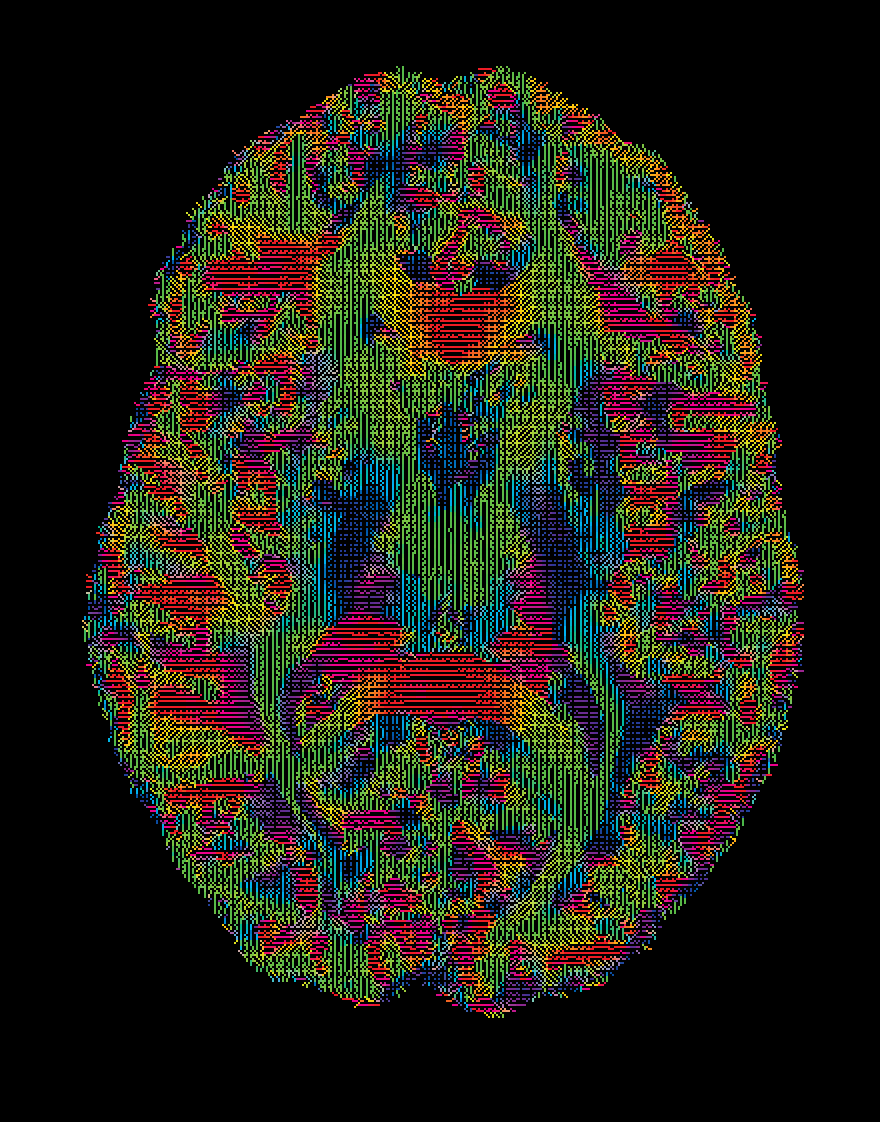

Diffusion tensor image of white matter fibre tracts in the brain of a musician.

Similarly, Dr Bronson Harry from MARCS is conducting MRI studies showing strong white matter connections between auditory and motor regions of the brain in people with high levels of synchronisation ability, demonstrating the close association between sound and movement. It is likely that these synchronisation tendencies served important functions in helping to coordinate and regulate group behaviours in our ancestors.